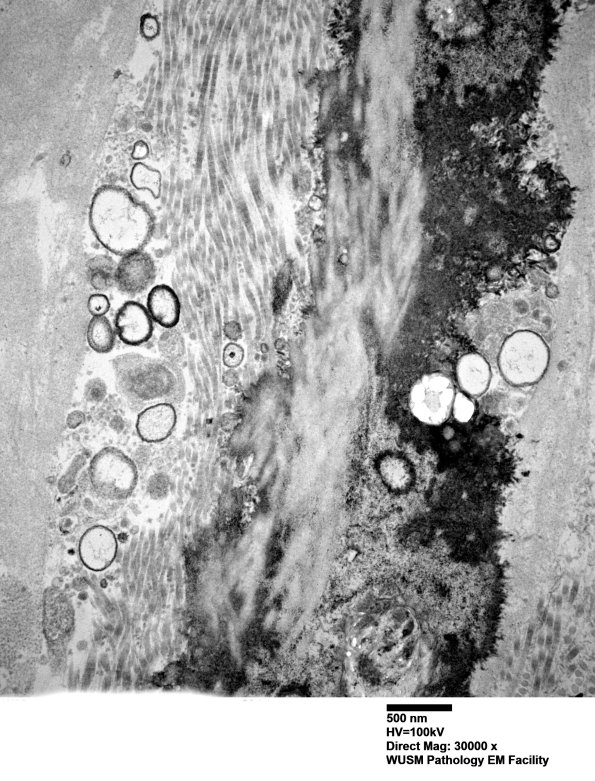

Higher magnification of image #6B1. (electron micrographs)